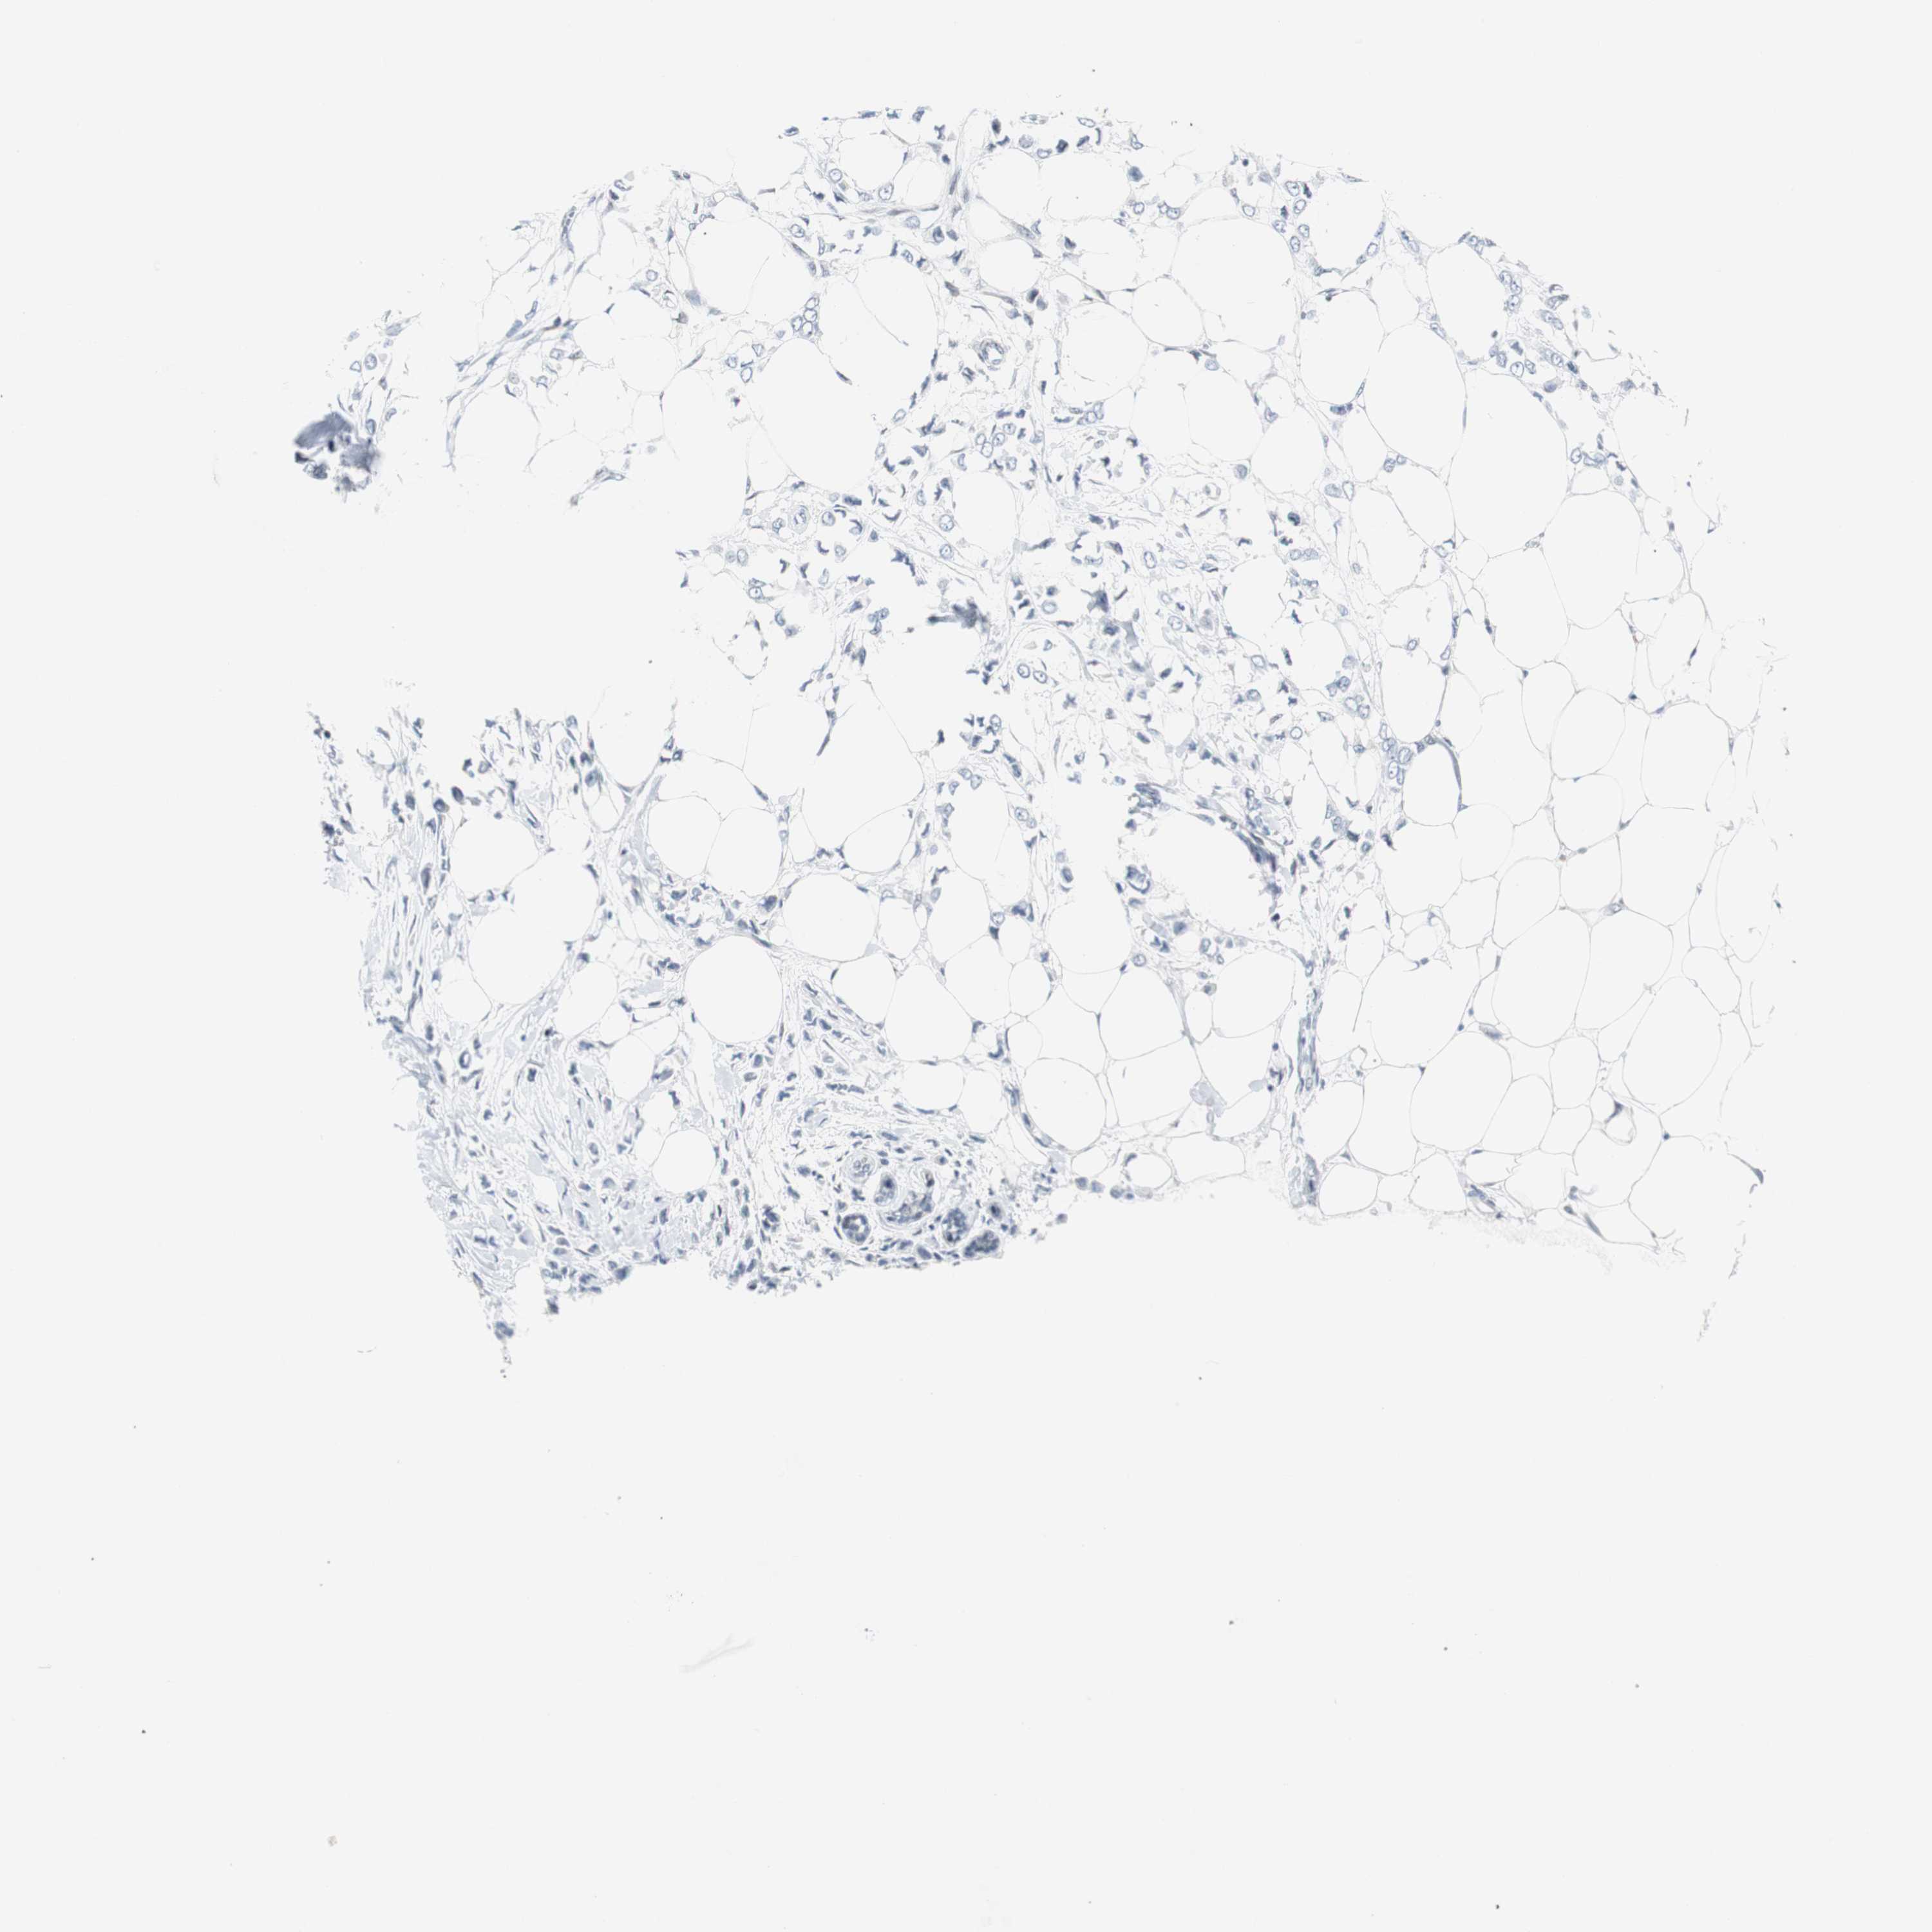

BRCA TCGA BRCA VALIDATION PROTEIN EXPRESSION